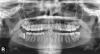

Aleonid Опубликовано 13 мая, 2012 Поделиться Опубликовано 13 мая, 2012 Здравствуйте, снимок зубов жены приложил. Планируем детей, а тут на снимке такой зуб мудрости смущает. Он в таком состоянии уже 2 года (снимок свежий 2мес давности, до этого 2х летней давности потеряли, но зуб там уже был). Ходили к платному ортодонту, он сказал удалять. Подскажите, обязательно ли его удалять, если за все годы он не тревожил, не болел. Может ли попасть инфекция в этот зуб, образоваться кариес или другие проблемы, если он так "спрятан"?. И если решать такую проблему, то лучше до беременности, или не имеет значение (обезболивающие вредны для чада, или техника все же дошла?).Спасибо за советы. Ссылка на комментарий

kriokov Опубликовано 13 мая, 2012 Поделиться Опубликовано 13 мая, 2012 удалять Вашей супруге надо все восьмеркинижняя 8 справа закрыта костью не полностью, инфицироваться будетлучше удалить до Ссылка на комментарий